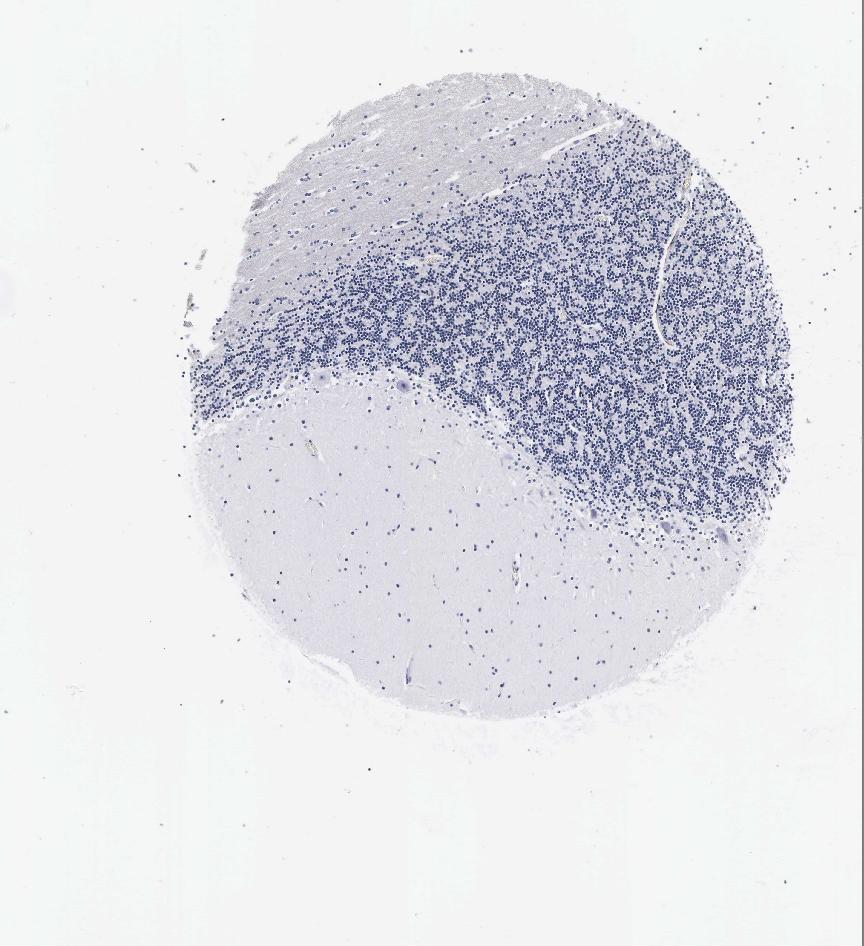

CEREBELLUM - Antibody stainingi

Antibody staining in the annotated cell types in the current human tissue is reported as not detected, low, medium, or high, based on conventional immunohistochemistry profiling in selected tissues. This score is based on the combination of the staining intensity and fraction of stained cells.

Each image is clickable and will lead to virtual microscopy that enables deeper exploration of all samples and also displays staining intensity scores, fraction scores and subcellular localization as well as patient and tissue information for each sample.

Antibody HPA001605Antibody CAB000008Antibody CAB000030

Purkinje cells Not detectedNot detectedNot detected

Cells in granular layer LowNot detectedNot detected

Cells in molecular layer LowNot detectedNot detected